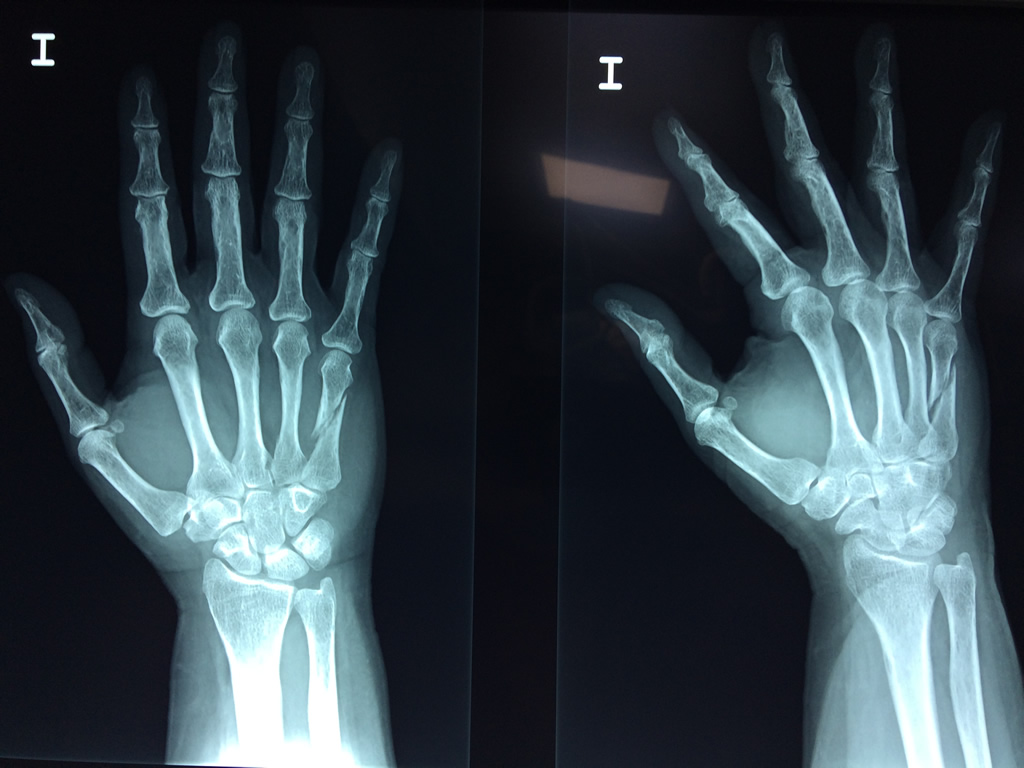

Cirugía de Fémur - Cirugías de Muñecas y Manos

Los procedimientos más comunes en cirugía de la mano son aquellos destinados a reparar traumatismos, incluyendo lesiones de tendones, nervios, vasos sanguíneos, y articulaciones; huesos fracturados; y quemaduras, cortes, y otros daños de la piel.